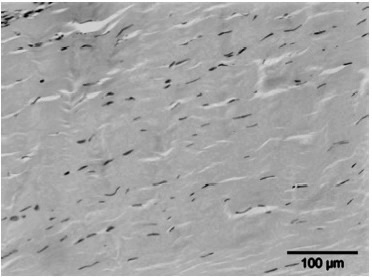

• Het stimuleren van de collageenproductie en het afvoeren van beschadigd collageen, wat resulteert in een verhoogde matrix-turnover.